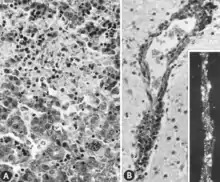

Acute infection of postnatal pigs, including pregnant dams that subsequently develop reproductive failure, is usually subclinical.[11][12][13][14][15][16] However, in young pigs and probably in older breeding stock as well, the virus replicates extensively and is found in many tissues and organs with a high mitotic index. Viral antigen is especially concentrated in lymphoid tissues[13][14] (Fig. 3A, B). Many pigs, irrespective of age or sex, have a transient, usually mild, leukopenia sometime within 10 days after initial exposure to the virus.[11][17][15][16] PPV and other structurally similar viruses have been identified in the feces of pigs with diarrhea.[18][19] However, there is no experimental evidence to suggest that PPV either replicates extensively in the intestinal crypt epithelium or causes enteric disease as do parvoviruses of several other species.[13][20] PPV also has been isolated from pigs with lesions described as vesiclelike. The causal role of PPV in such lesions has not been clearly defined.[21]

Replication of PPV in vitro is cytocidal and characterized by "rounding up," pyknosis, and lysis of cells (Fig. 1A). Many of the cell fragments often remain attached, eventually giving the affected culture a ragged appearance. Intranuclear inclusions develop[31] but they are often sparsely distributed.[39] Infected cultures may hemadsorb slightly[31] (Fig. 1B). Cytopathic changes are extensive when cell culture-adapted virus is propagated under appropriate conditions. However, on initial isolation several serial passages of the virus[31] or, better, the infected culture may be necessary before the effects are recognized. The use of immunofluorescence (IF) microscopy greatly increases the likelihood of detecting minimally infected cultures.[40][41]

There are numerous macroscopic changes in fetuses infected before they become immunocompetent (Fig. 6). These include a variable degree of stunting and sometimes an obvious loss of condition before other external changes are apparent; occasionally, an increased prominence of blood vessels over the surface of the fetus due to congestion and leakage of blood into contiguous tissues; congestion, edema, and hemorrhage with accumulation of serosanguineous fluids in body cavities; hemorrhagic discoloration becoming progressively darker after death; and dehydration (mummification). Many of these changes also apply to the placenta. Microscopic lesions consist primarily of extensive cellular necrosis in a wide variety of tissues and organs[95][98] (Fig. 7A). Inflammation[98] and intranuclear inclusions[95] also have been described.

In contrast, macroscopic changes have not been reported for fetuses infected after they become immunocompetent for PPV. Microscopic lesions are primarily endothelial hypertrophy[97] and mononuclear cell infiltrations consistent with an immune response.[97][98] Meningoencephalitis characterized by perivascular cuffing with proliferating adventitial cells, histiocytes, and a few plasma cells was seen in the gray and white matter of the cerebrum and in the leptomeninges of PPV-infected stillborn pigs. These lesions were believed to be pathognomonic for PPV infection.[24] Similar lesions have been observed in PPV-infected, live fetuses collected late in gestation[97][98] (Fig. 7B).